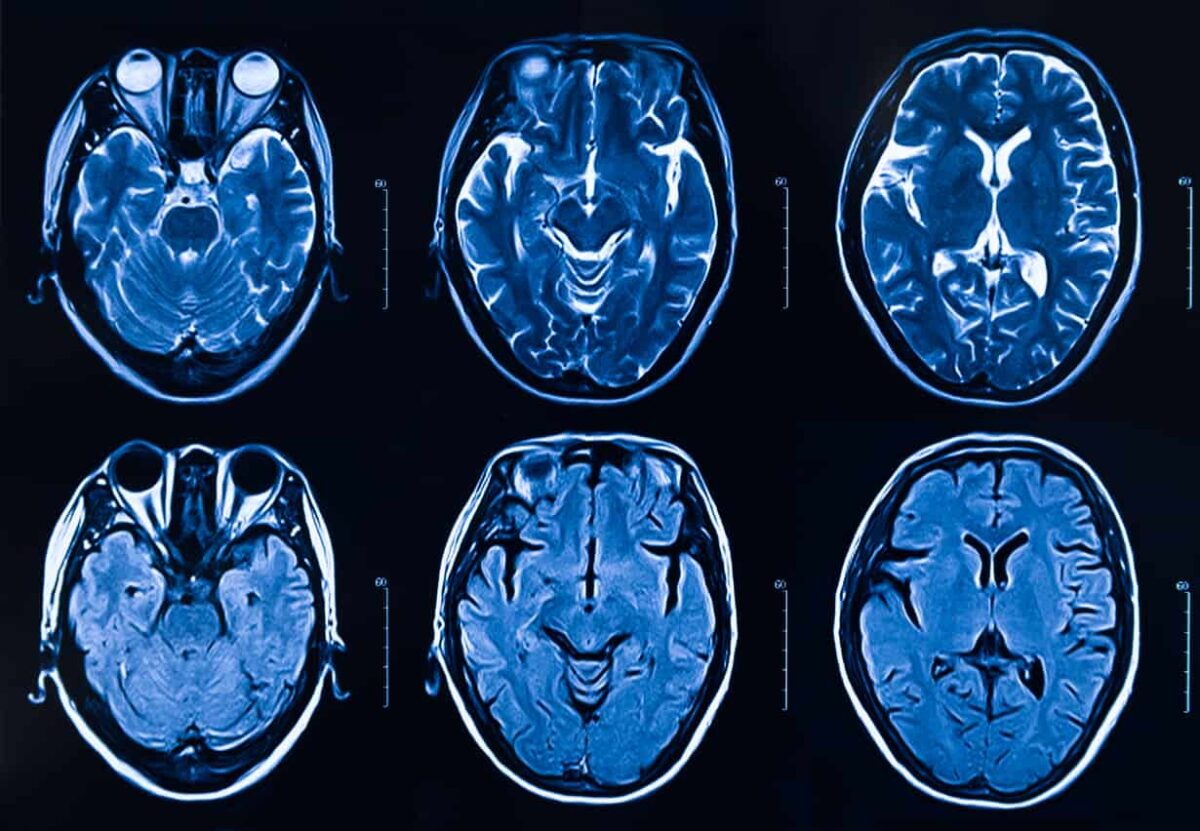

November 2020, Episode 77: Have you been told you have white matter lesions on your MRI findings? What does it mean? How many of us have this finding? Should we be concerned? Dr. Lindsay Weitzel talks with Dr. Vince Martin about what these lesions we see on our MRI reports mean.